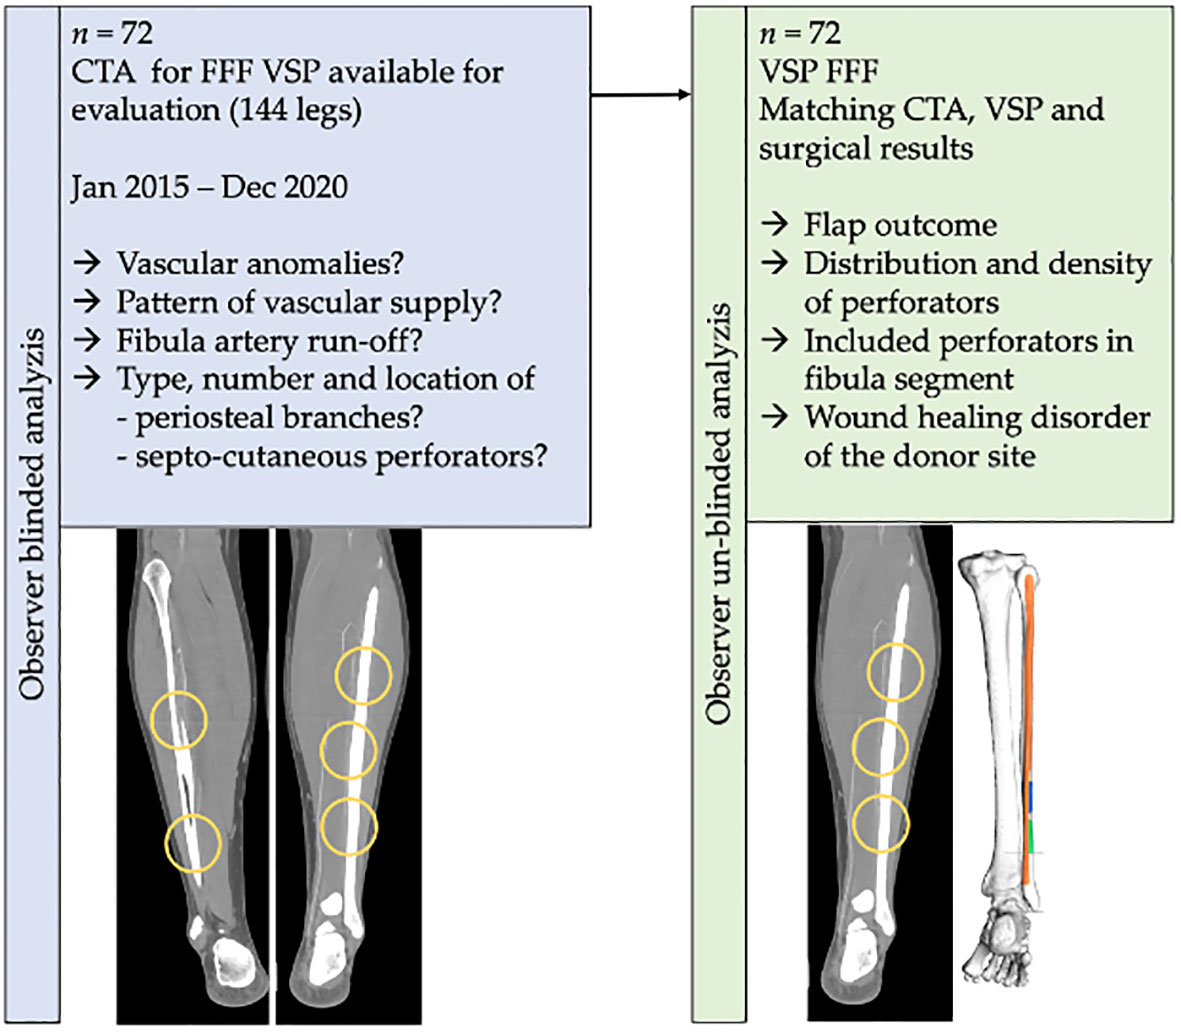

eb4acaabee778636e6a97f8010df93。大腿骨頸部骨折の手術【手外科・外傷】 | おおさかグローバル。Frontiers | Impact of Periosteal Branches and Septo。「大腿骨近位部骨折 : 大腿骨頚部・転子部・転子下骨折の手術手技」高平 尚伸 / 最上 敦彦 / 神田 章男 / 北田 真平定価: ¥ 14000#高平尚伸 #高平_尚伸 #最上敦彦 #最上_敦彦 #神田章男 #神田_章男 #北田真平 #北田_真平 #本 #自然/医療・薬学・健康 サージカルテクニック裁断済みです。裁断にご理解頂ける方のみご購入よろしくお願いします。Treatment of moderate and severe hallux valgus by performing。書き込みは見たところございません。ペリー 歩行分析 正常歩行と異常歩行。アシックス やり投げ ジャベリンプロ3。